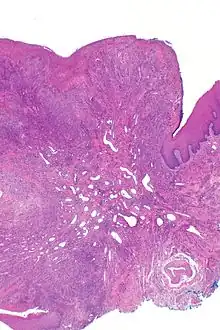

Eosinophilic ulcer of the oral mucosa – H&E stain

Eosinophilic ulcer of the oral mucosa (also known as traumatic eosinophilic granuloma[1]) is a condition characterized by an ulcer with an indurated and elevated border.[2] The lesion might be tender, fast-growing and the patient often not be aware of any trauma in the area.